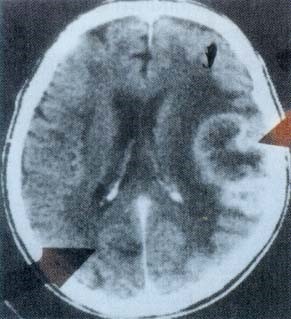

CT-Bild

Lösung eines Revierkonfliktes = Herzinfarkt